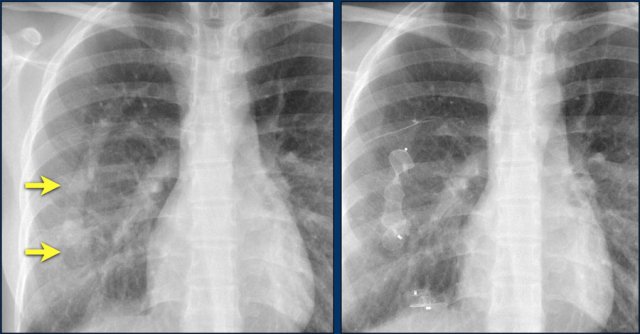

First study the images.

Then continue reading.

The findings are:

• Two epicardial leads connected to pacemaker

• ICD

• two leads to right ventricular apex

• one lead contains two shock coils

• tricuspid valve (arrows)

• mitral valve